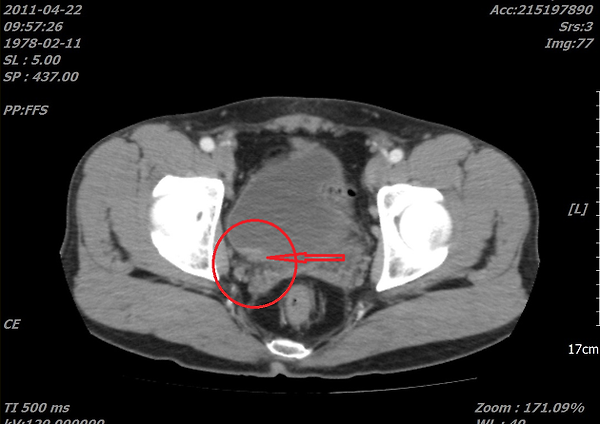

위사진은 암으로 추측되는부분이라도 개인병원 의사가 찾아주신 자료 중 하나입니다.

이게 맞을까요? 첫번째  2011년, 그다음 2015년 세번째도 2011년 그다음 2016년입니다. ....

올려주신 영상은 PELVIS 쪽의 조영증강(ENHANCED) CT 검사네요.

첫째, 셋째 사진이 2011(초진검사) 하신 영상이고,

둘째 ,넷째 사진이 15,16년 사진이시죠.

사진이 명확치 않아 확인지 조금 어렵지만

사진상에 보이는 것은 네번째 마지막 사진에만 확실한 종양의심부분이 관찰이 되고 있습니다.

추가질문  「 좀 더 선명한 사진인데....다시한번 봐주시겠습니까..... 」 에 대한 답변입니다.

아. 정확히 보이시네요.

첫번째 사진 2011년 4월22일 ENHANCE CT 영상에서도

동그라미 쳐진 부분(화살표) 부분이 조영증강된 것이 확인이 됩니다.

나머지도 보시기 쉽게 동그라미 표시를 해드렸습니다.